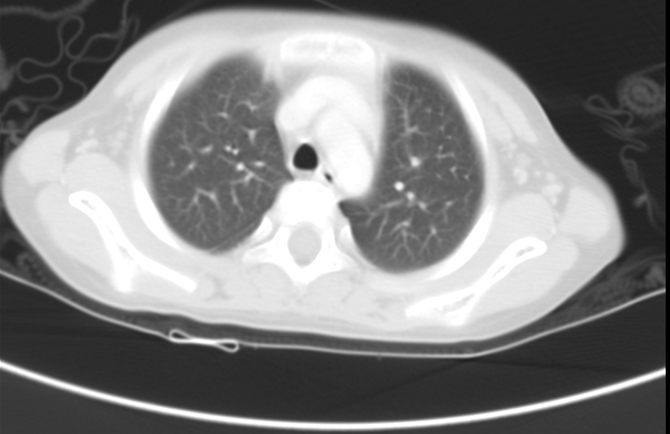

胸部+上下腹部CT检查:肝右叶增大,右后叶可见软组织影,约9.8×9.0×8.6cm,边界欠清晰,密度不均匀,其内可见钙化灶,增强扫描不均匀强化,考虑肝母细胞瘤;下腔静脉内低密度影,考虑瘤栓;双肺多发结节影,长径约2~11mm,边界清晰,考虑转移瘤;前纵膈软组织影,考虑未退化胸腺组织。

图1 胸部+上下腹部CT